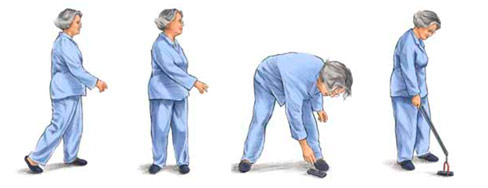

Как научиться ходить на костылях

Для успешного передвижения на костылях их необходимо правильно отрегулировать. Во время ходьбы старайтесь переносить вес тела на руки, избегая перегрузки подмышечных впадин. При использовании канадок следите за тем, чтобы рукоять всегда была направлена вперед, а манжета надежно фиксировала предплечье.

Поддерживайте прямую позу спины и головы, избегая наклона вперед. В процессе движения костыли нужно передвигать одновременно примерно на 30 см вперед и слегка в стороны. Затем вес тела переносится на руки, и тело перемещается вперед.

Начинайте вставать на пятку, удерживая костыли сзади. Затем опирайтесь на здоровую ногу и размещайте костыли впереди.